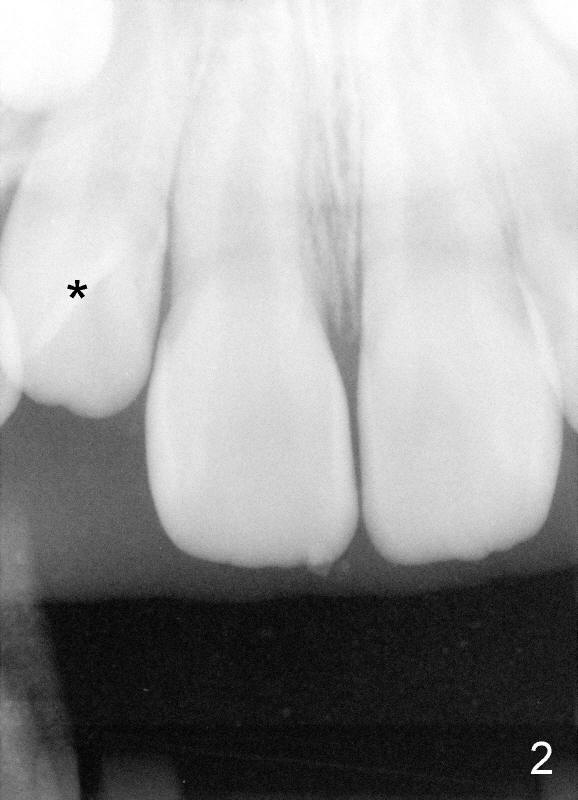

Panramic X-ray was taken when Edward was 6 years 5 months old (Fig.1). His parents and he himself found that the upper right lateral did not erupt at the age of 9 years 2 months (Fig.2-4: *). Gingivectomy was performed using soft tissue laser to expose the incisal edge of the lateral. Five months later, the lateral has erupted partially (Fig.5-8), but the family is concerned about the cosmetic issue. It appears that the upper midline has shifted to the right (Fig.6). Periapical film is planned to take to confirm the relationship between the canine and the lateral.